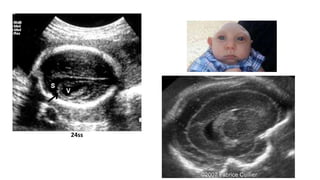

TRANSTORNOS DE PROLIFERACIÓN: MACROCEFALIA

• Head circumference above the 98th percentile or more than 2

standard deviations above the mean.

• Macrocephaly is relatively frequent in children and adults and is a

common cause for genetic consultation.

• The diagnosis assumes that other obvious causes of head

enlargement, such as hydrocephalus and cerebral tumors, have been

excluded. Usually, macrocephaly is familial and benign and frequently

it manifests only late in pregnancy or after delivery.